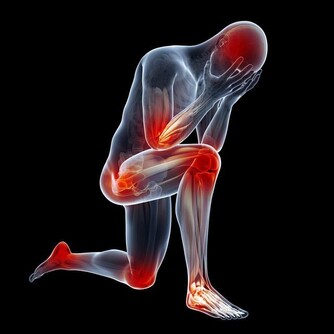

冬季可以說是前列腺炎的最高發季節,主要就是指前列腺受涼而引起,

要知道的是,受涼對前列腺的影響非常大,可以直接的影響到前列腺的功能,

所以,冬季預防前列腺炎,最關鍵的就是避免受涼,注意保暖。下面就冬季前列腺炎的預防方式進行介紹: